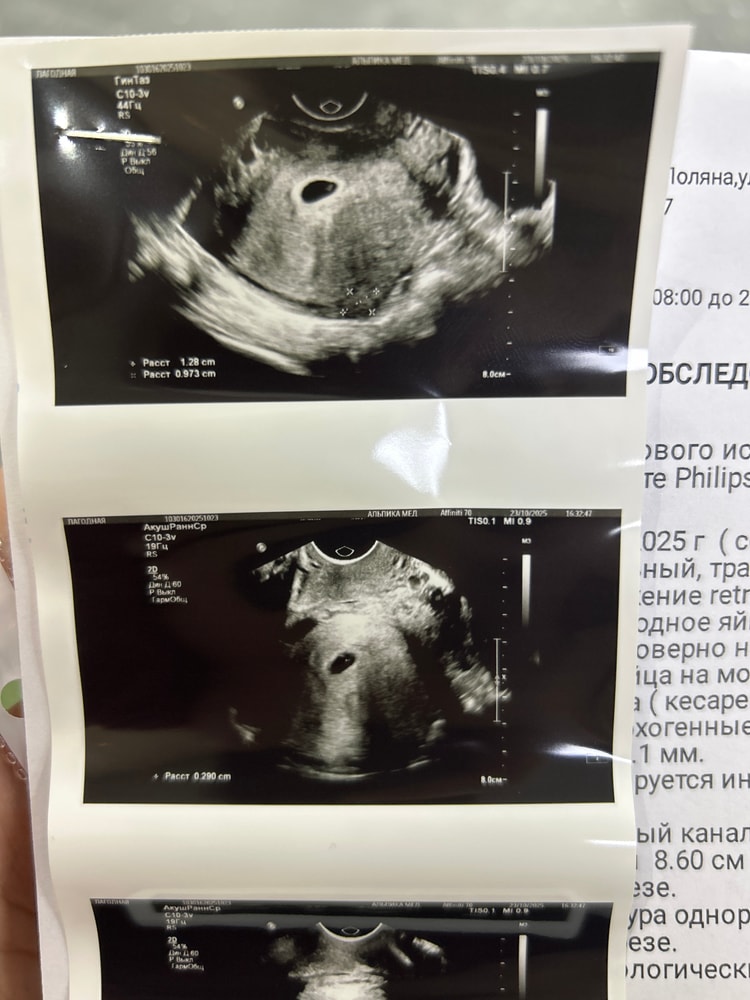

Первое узи ♥️

УЗИ, КТГ, доплерБеременность маточная, сроку соответствует 6 недель, но эмбриончика не видно, желточный мешочек есть, формы четкие и ровные, я немного расстроилась ,тк хотела сб послушать 🥹

но слава богу что ни гиматом ни отслоек нет, НО оказалась миома.. мне врач говорил что какое-то странное образование в полости, после искусственных родов .. оказалась она. Никогда небыло миом, это опасно? Страшно?

а вот моя бусинка🩷